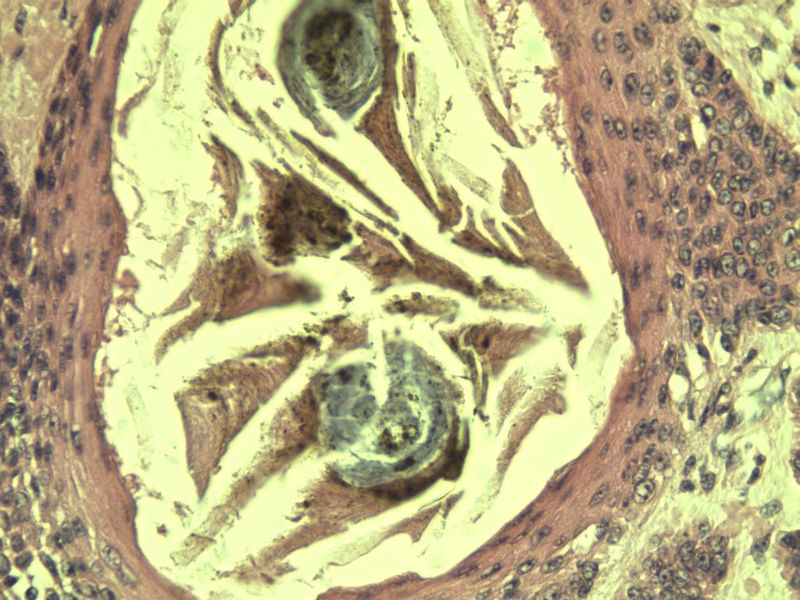

这是另外一个  75岁 男性 脸上有一直径0.8cm新生物 是鳞癌吗? 感觉细胞异型性不够大.

第二例:基底细胞癌

第二例,两种成分,1、毛发上皮瘤;2、皮内痣。

第一例考虑毛母细胞瘤,第二例考虑基底细胞癌。

第一例:毛母细胞瘤;第二例:基底细胞癌

第一例,毛发上皮瘤;第二例,基底细胞癌。

1.BCC.  2.BCC.

二基底细胞癌。

两例均为BCC